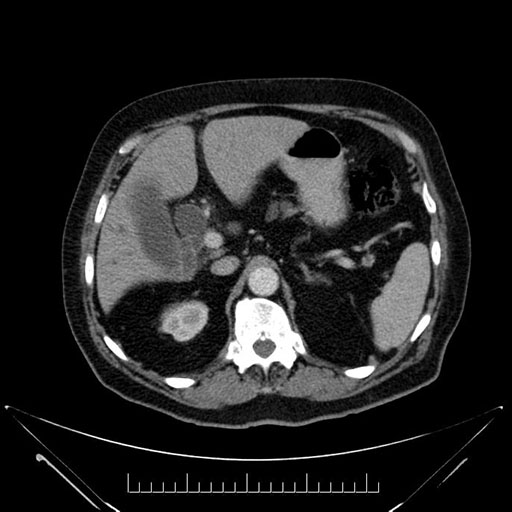

Imaging Analysis

Look through the patient's CT scan to identify any areas of concern for the necessary procedure.

Based on your CT findings, which issue(s) would give reason for "planned slowing down moment(s)" in this case?

Considering a standard Whipple procedure, what step(s) of the operation would you do differently in this case?